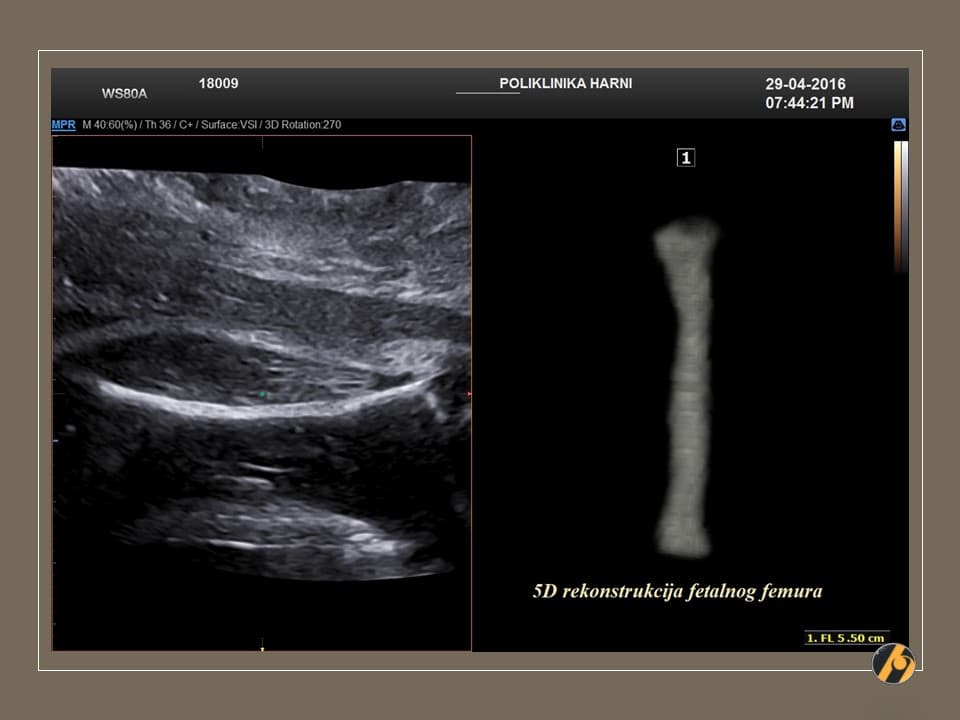

Fetus je dug približno 25 do 28 cm i težak oko 350 do 390 g. Razvijaju se okusni pupoljci, probavni sustav i krvne stanice.

U 21. tjednu trudnoće beba je duga približno 25 do 28 centimetara i teška oko 350 do 390 grama. Veličinom se često uspoređuje s većom bananom ili mrkvom.